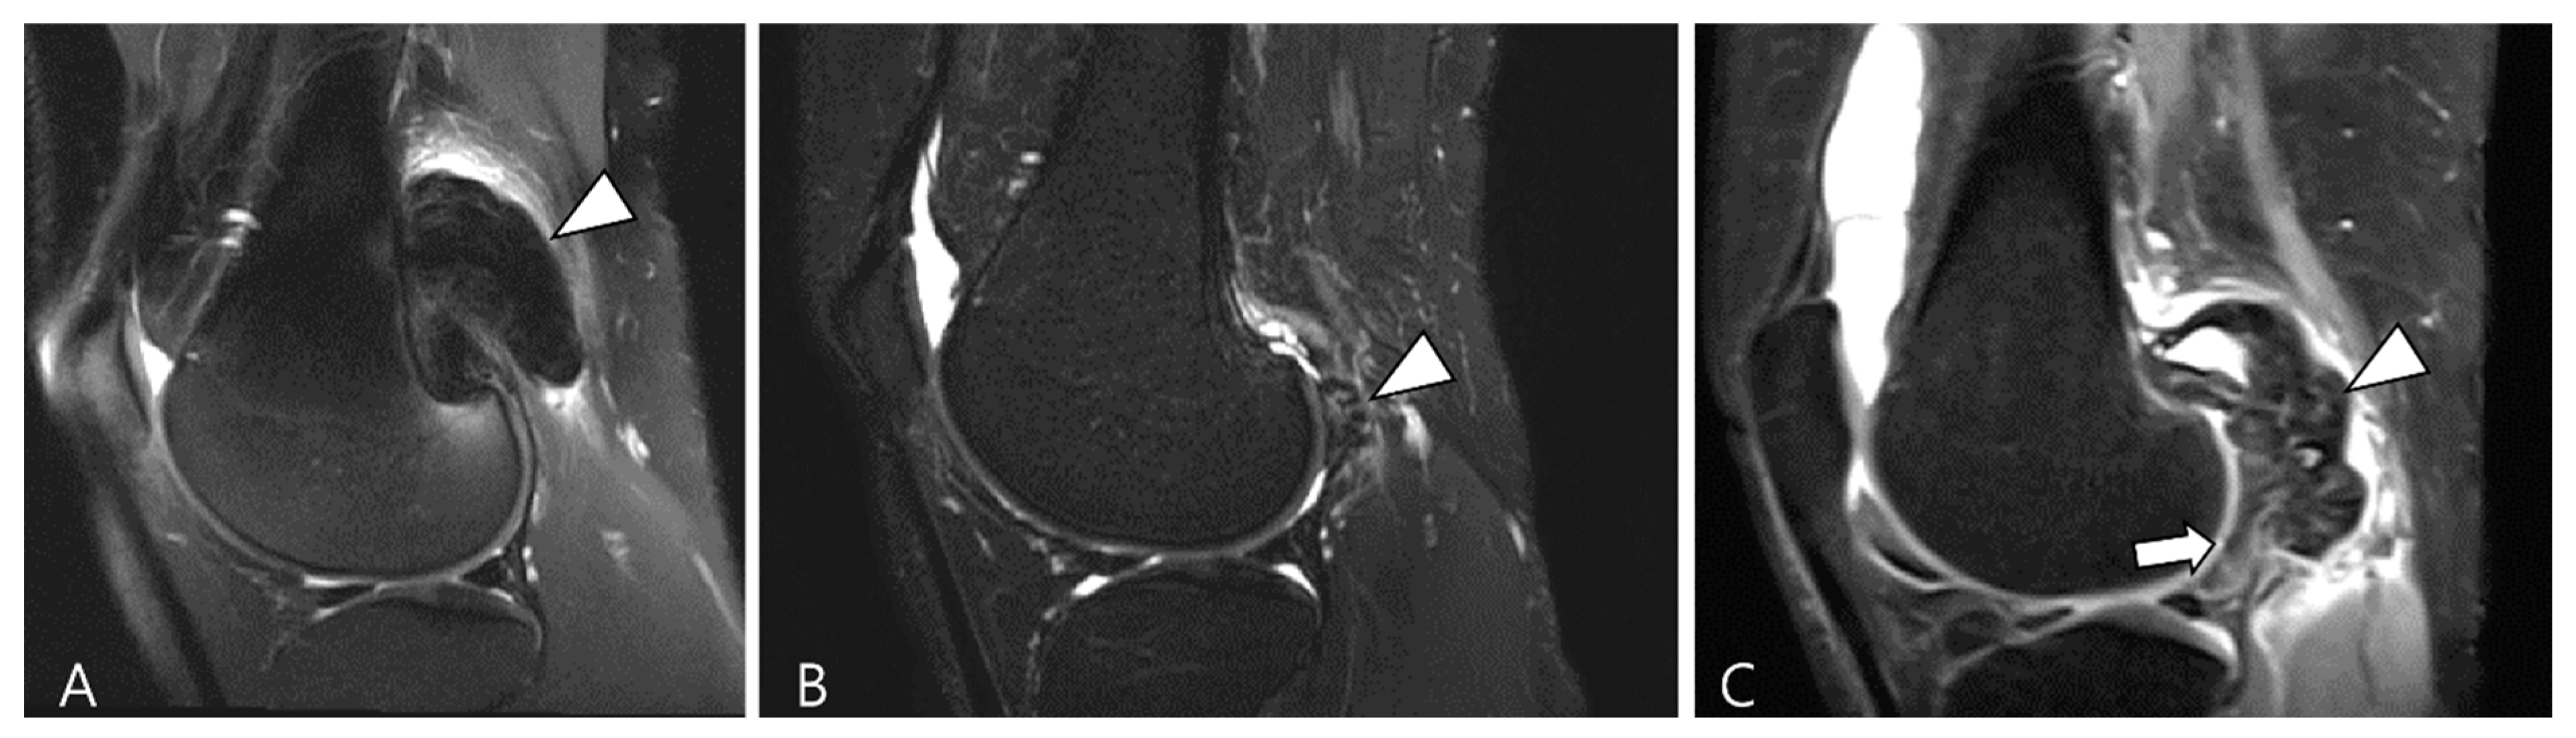

In terms of surgical outcome, local recurrence is defined as the presence of new disease after synovectomy or the observation of growing residual disease on a follow-up MRI scan [18]. Diffuse synovial thickening within the first 6 months can be equivocal for residual disease due to associated reactive synovitis. However, suspicion of disease recurrence should arise if there is evidence of growing, enhancing solid, and nodular synovial thickening (Figure 18) [1].

Figure 18.

Serial T2WI follow-ups for D-TSGCT. (A) Initial MRI shows a low SI mass at the popliteal fossa (arrowhead). (B) After En bloc excision, the first follow-up MRI (1 year) shows small low SI nodule at the posterior joint capsule (arrowhead). (C) Second follow-up MRI (3 years) shows recurrent mass extra-articularly (arrowhead) and extensive nodular thickening intra-articularly (arrow).

D-TSGCT also poses a risk for the early development of osteoarthritis, particularly in the knee, hip, and ankle [80]. Recurrent disease is likely to necessitate multiple surgeries, leading to significant joint morbidity that could expedite the degenerative process associated with D-TSGCT toward secondary osteoarthritis (Figure 19) [81]. Lin et al. [81] reported that nearly 30% of patients underwent at least two surgeries during follow-up, and the risk of recurrent surgery was twice as high in patients with osteoarthritis compared with those without. This underscores the imperative for effective non-surgical treatment options for D-TSGCT, especially in patients with secondary osteoarthritis [81].

Figure 19.

A 47-year-old male with D-TSGCT in the right hip joint. (A) Initial coronal fat-suppressed T2WI shows a tiny low SI nodular synovial thickening in the right hip joint (arrowheads). (B) After synovectomy, follow-up CT after 4 years shows the development of osteoarthritis (arrows) in the right hip joint.